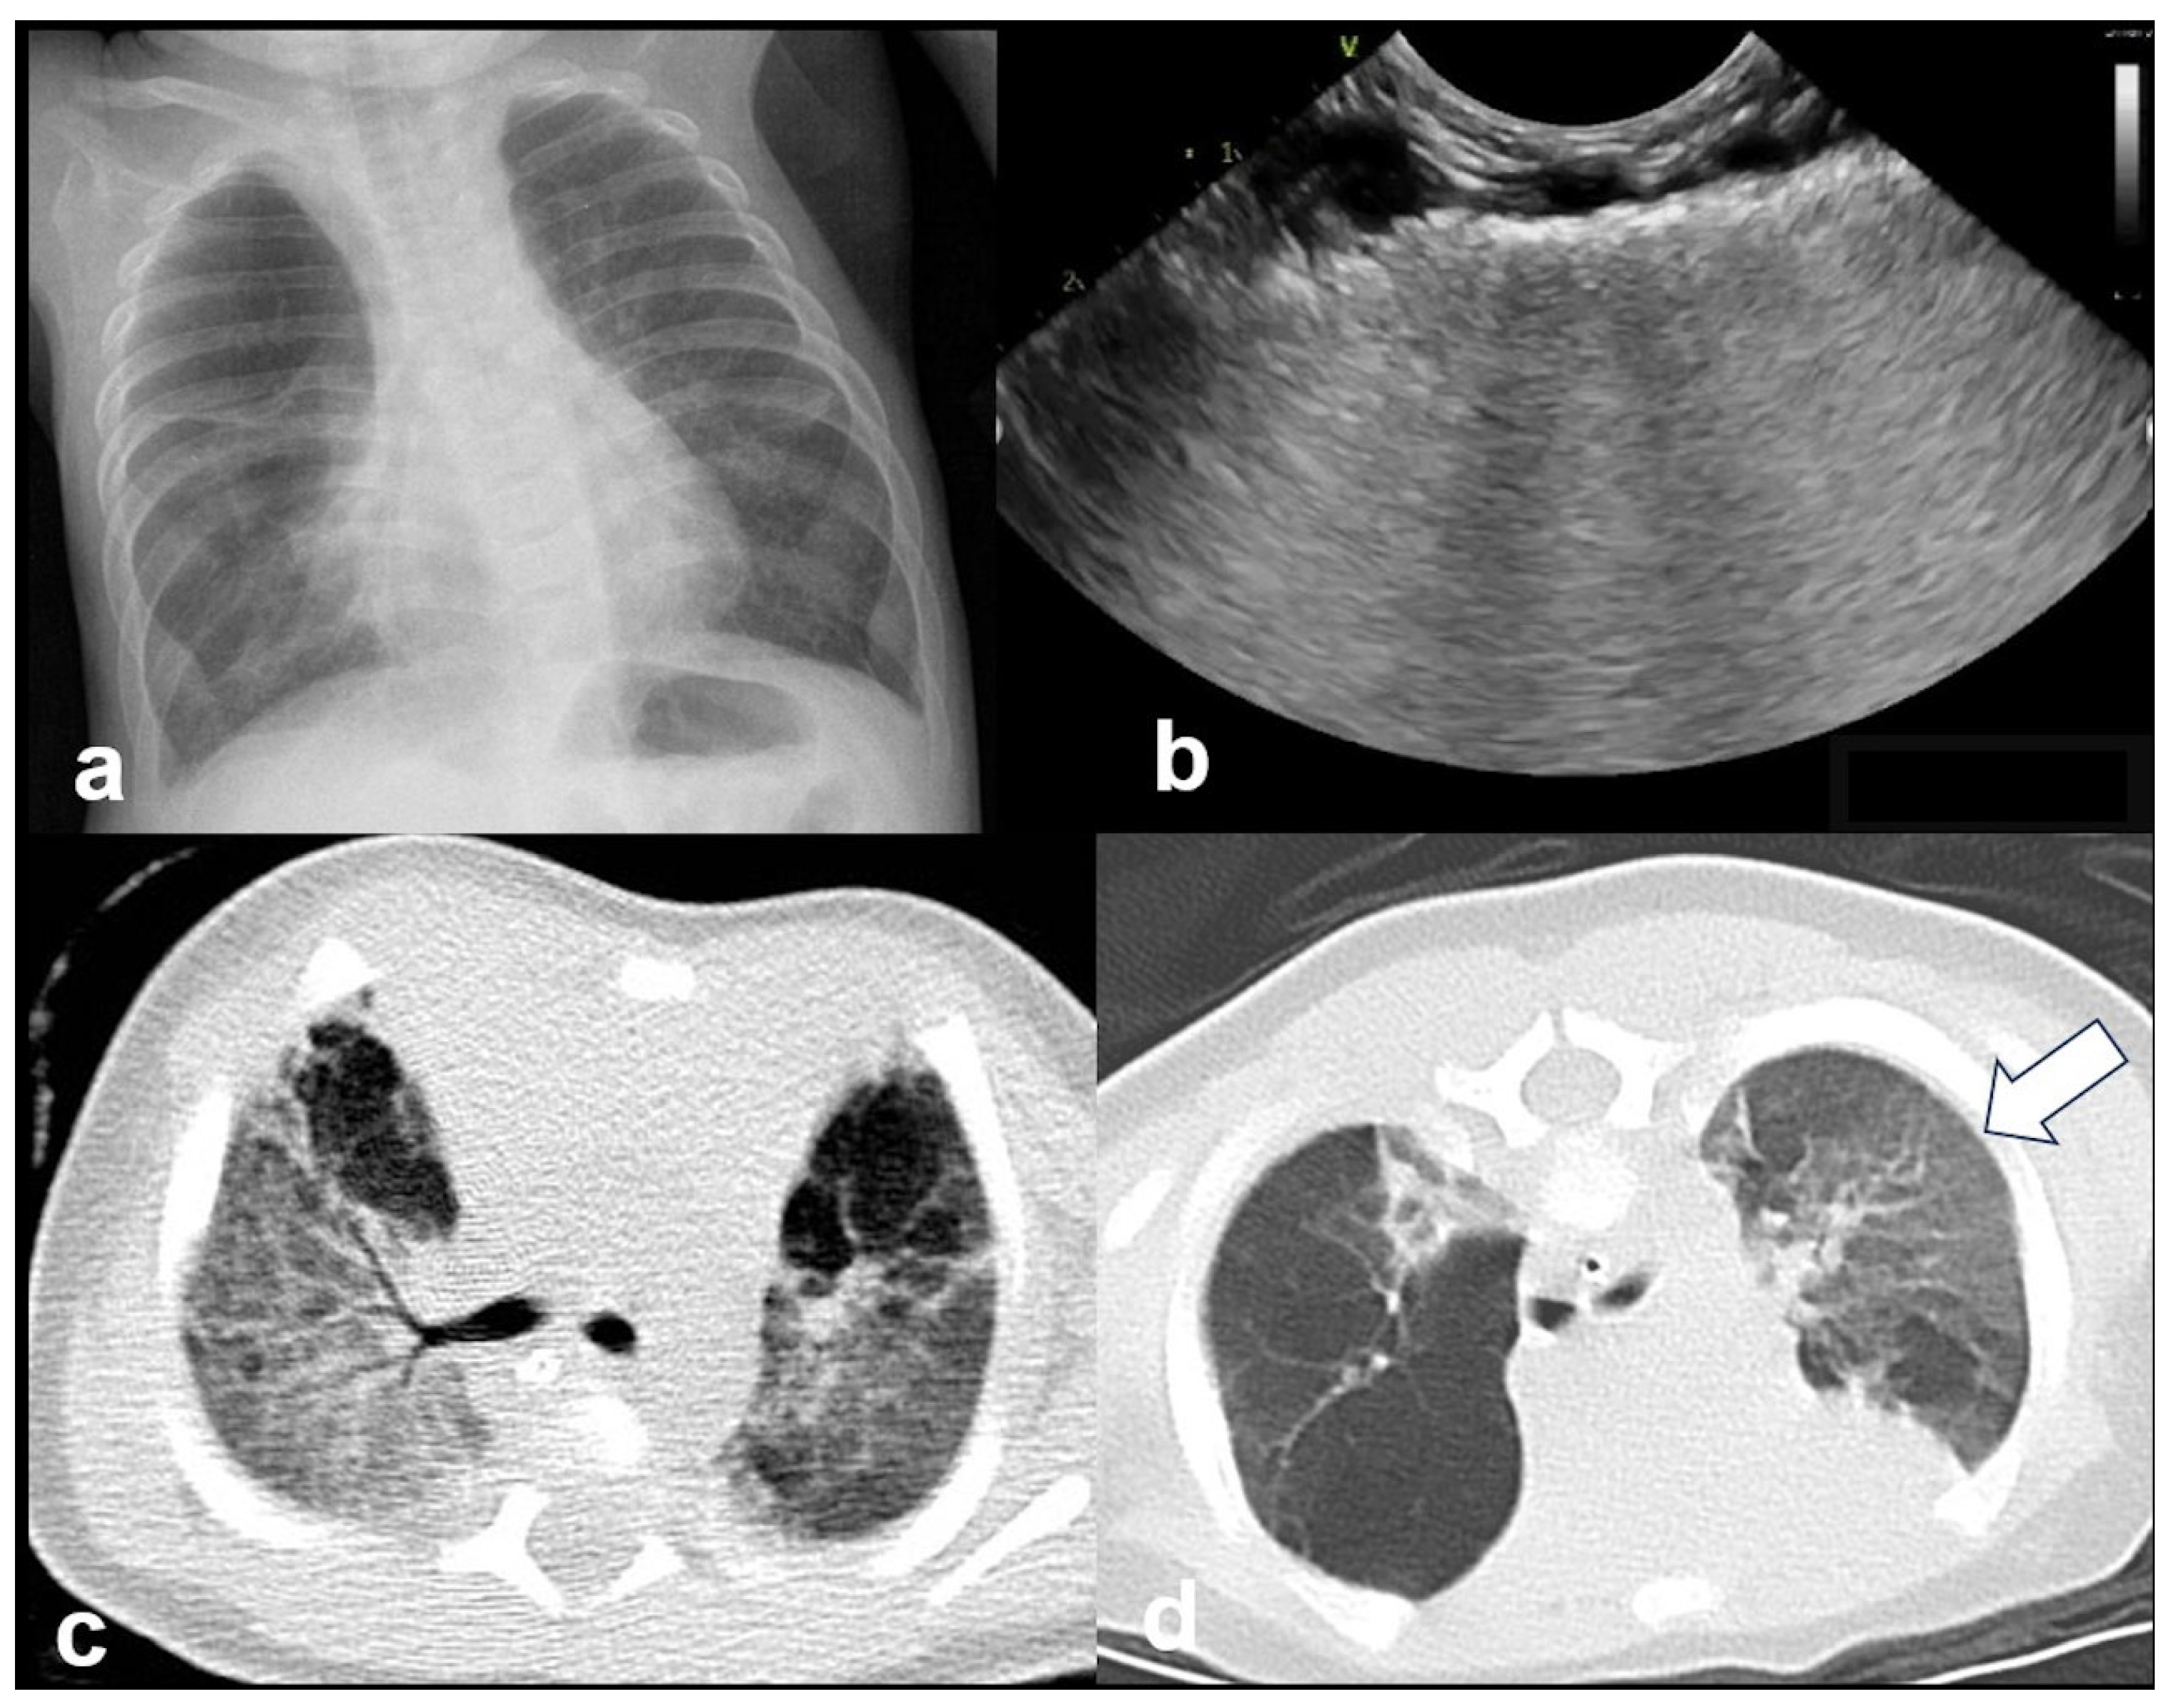

3.2.7. Lung Consolidation

3.2.8. Pneumothorax